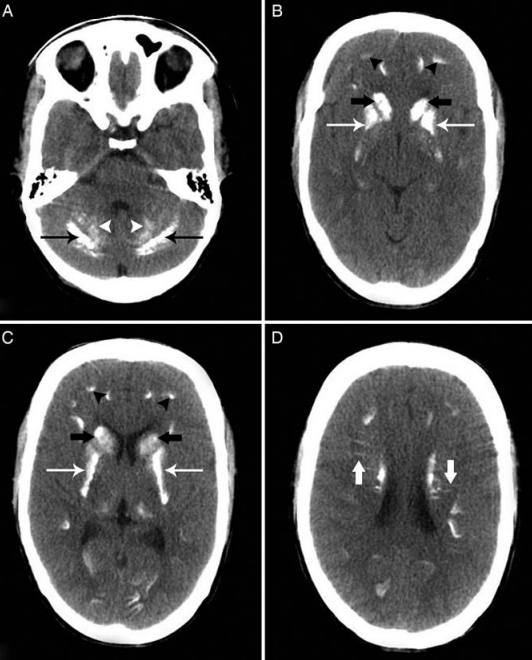

Рис.1. Болезнь Фара (стриопаллидодентатный кальциноз). На нативной КТ в аксиальной плоскости визуализируются двусторонние симметричные участки кальцификации в гемисферах мозжечка (тонкие черные стрелки) (рис.А). Также обратите внимание на кальцификацию обоих зубчатых ядер (головки стрелок) (рис.А). Наблюдается обширная двусторонняя кальцификация в головках хвостатых ядер (толстые черные стрелки) (рис.B и C), скорлупе и латеральных бледных шарах (тонкие белые стрелки) с относительно интактными медиальными отделами бледных шаров и таламуса (рис. B). Также имеется кальцификация на границе серого и белого вещества (черные стрелки) (рис.B). Видно, что линейные участки кальцификации простираются перпендикулярно хвостатым ядрам (толстые белые стрелки) (рис.D).